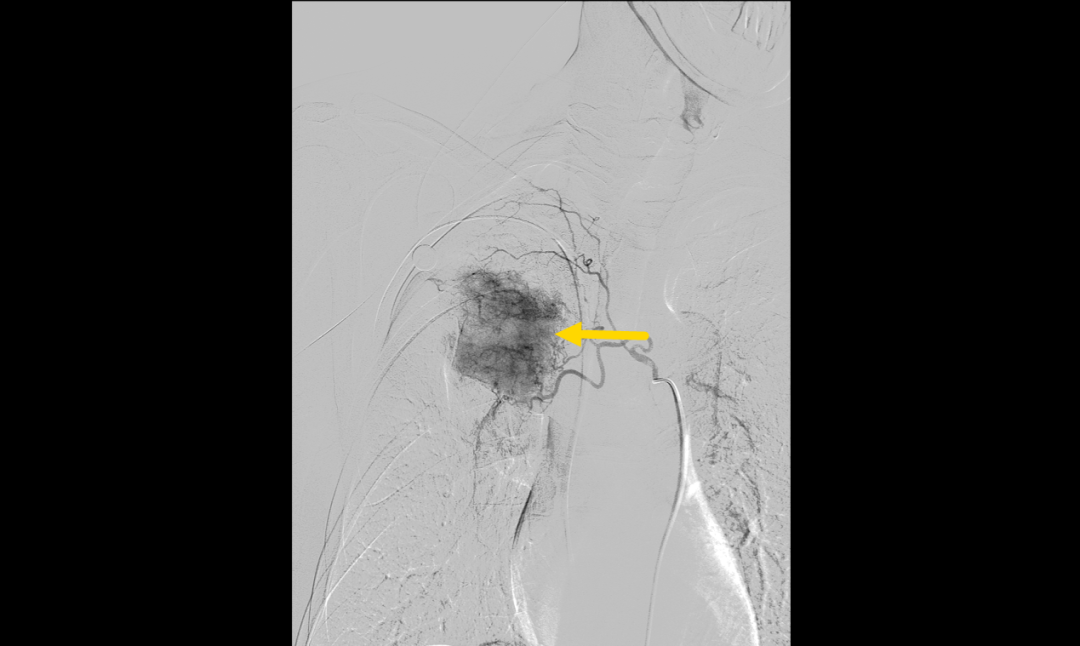

▲BACE术前肿瘤血供丰富(黄色箭头为肿瘤血供丰富处)

面对复杂的病情,呼吸与危重症医学科学科带头人、省医派驻专家罗少华指出,患者基线肿瘤分期属IIIB期,常规的免疫+化疗方案疗效不佳,存在肿瘤耐药情况,可尝试载药微球支气管动脉化疗栓塞术,以期缩小病灶,为手术创造机会,呼吸介入团队经过缜密的术前讨论和评估,认为患者有BACE适应证。征得患者及家属充分知情同意后,呼吸介入团队成功为患者实施了BACE手术,术后造影显示肿瘤区造影剂滞留,血流速度明显减慢,封堵效果满意,标志着手术取得圆满成功。